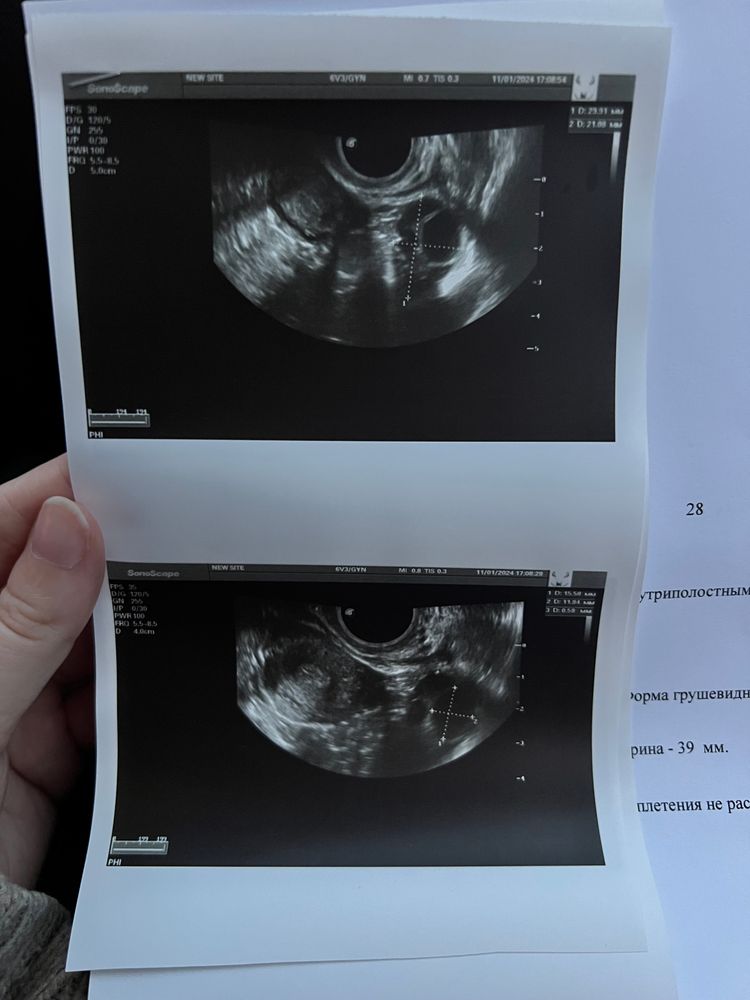

Мари, извиняюсь не так написала вот заключение Изображение

Лалала, да написано в шейке матки